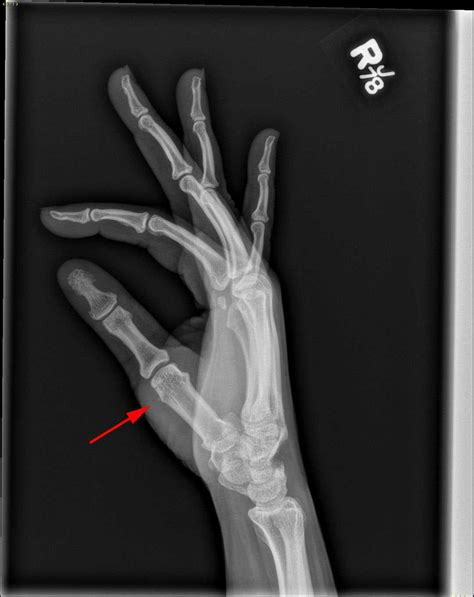

• X-rays: Used to rule out fractures or bone chips associated with the injury.